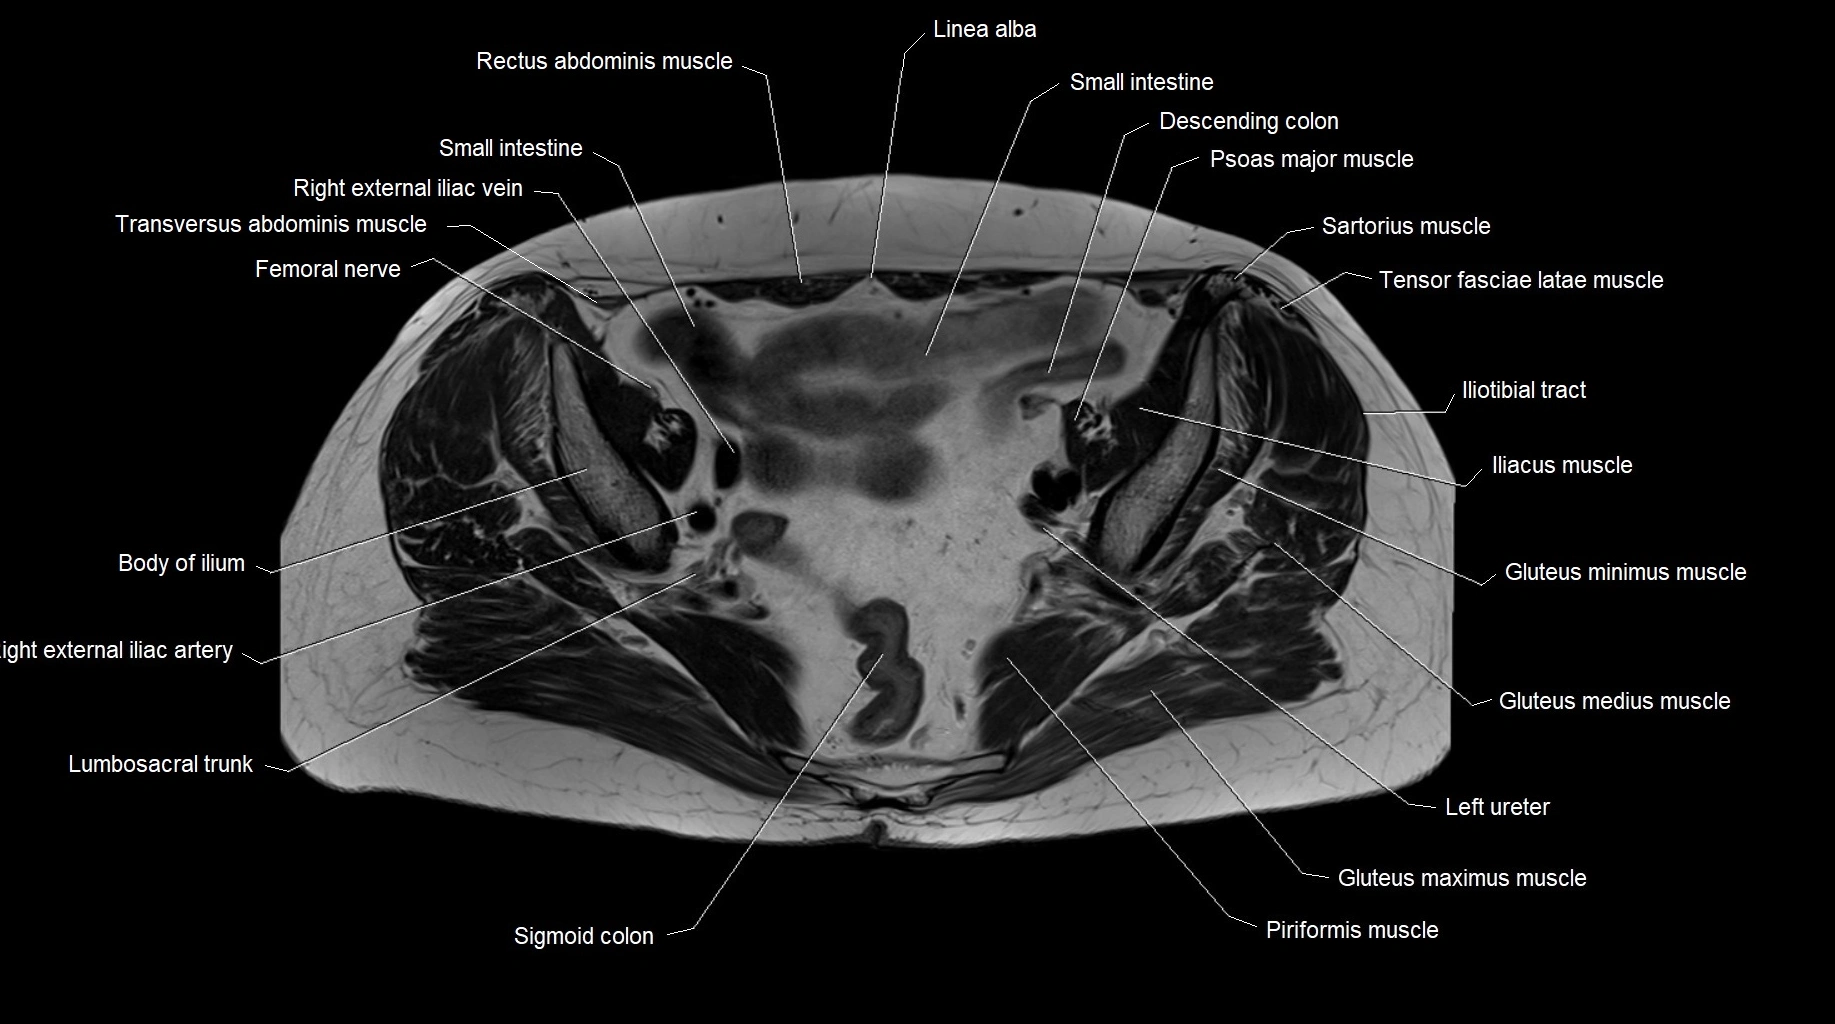

MRI images